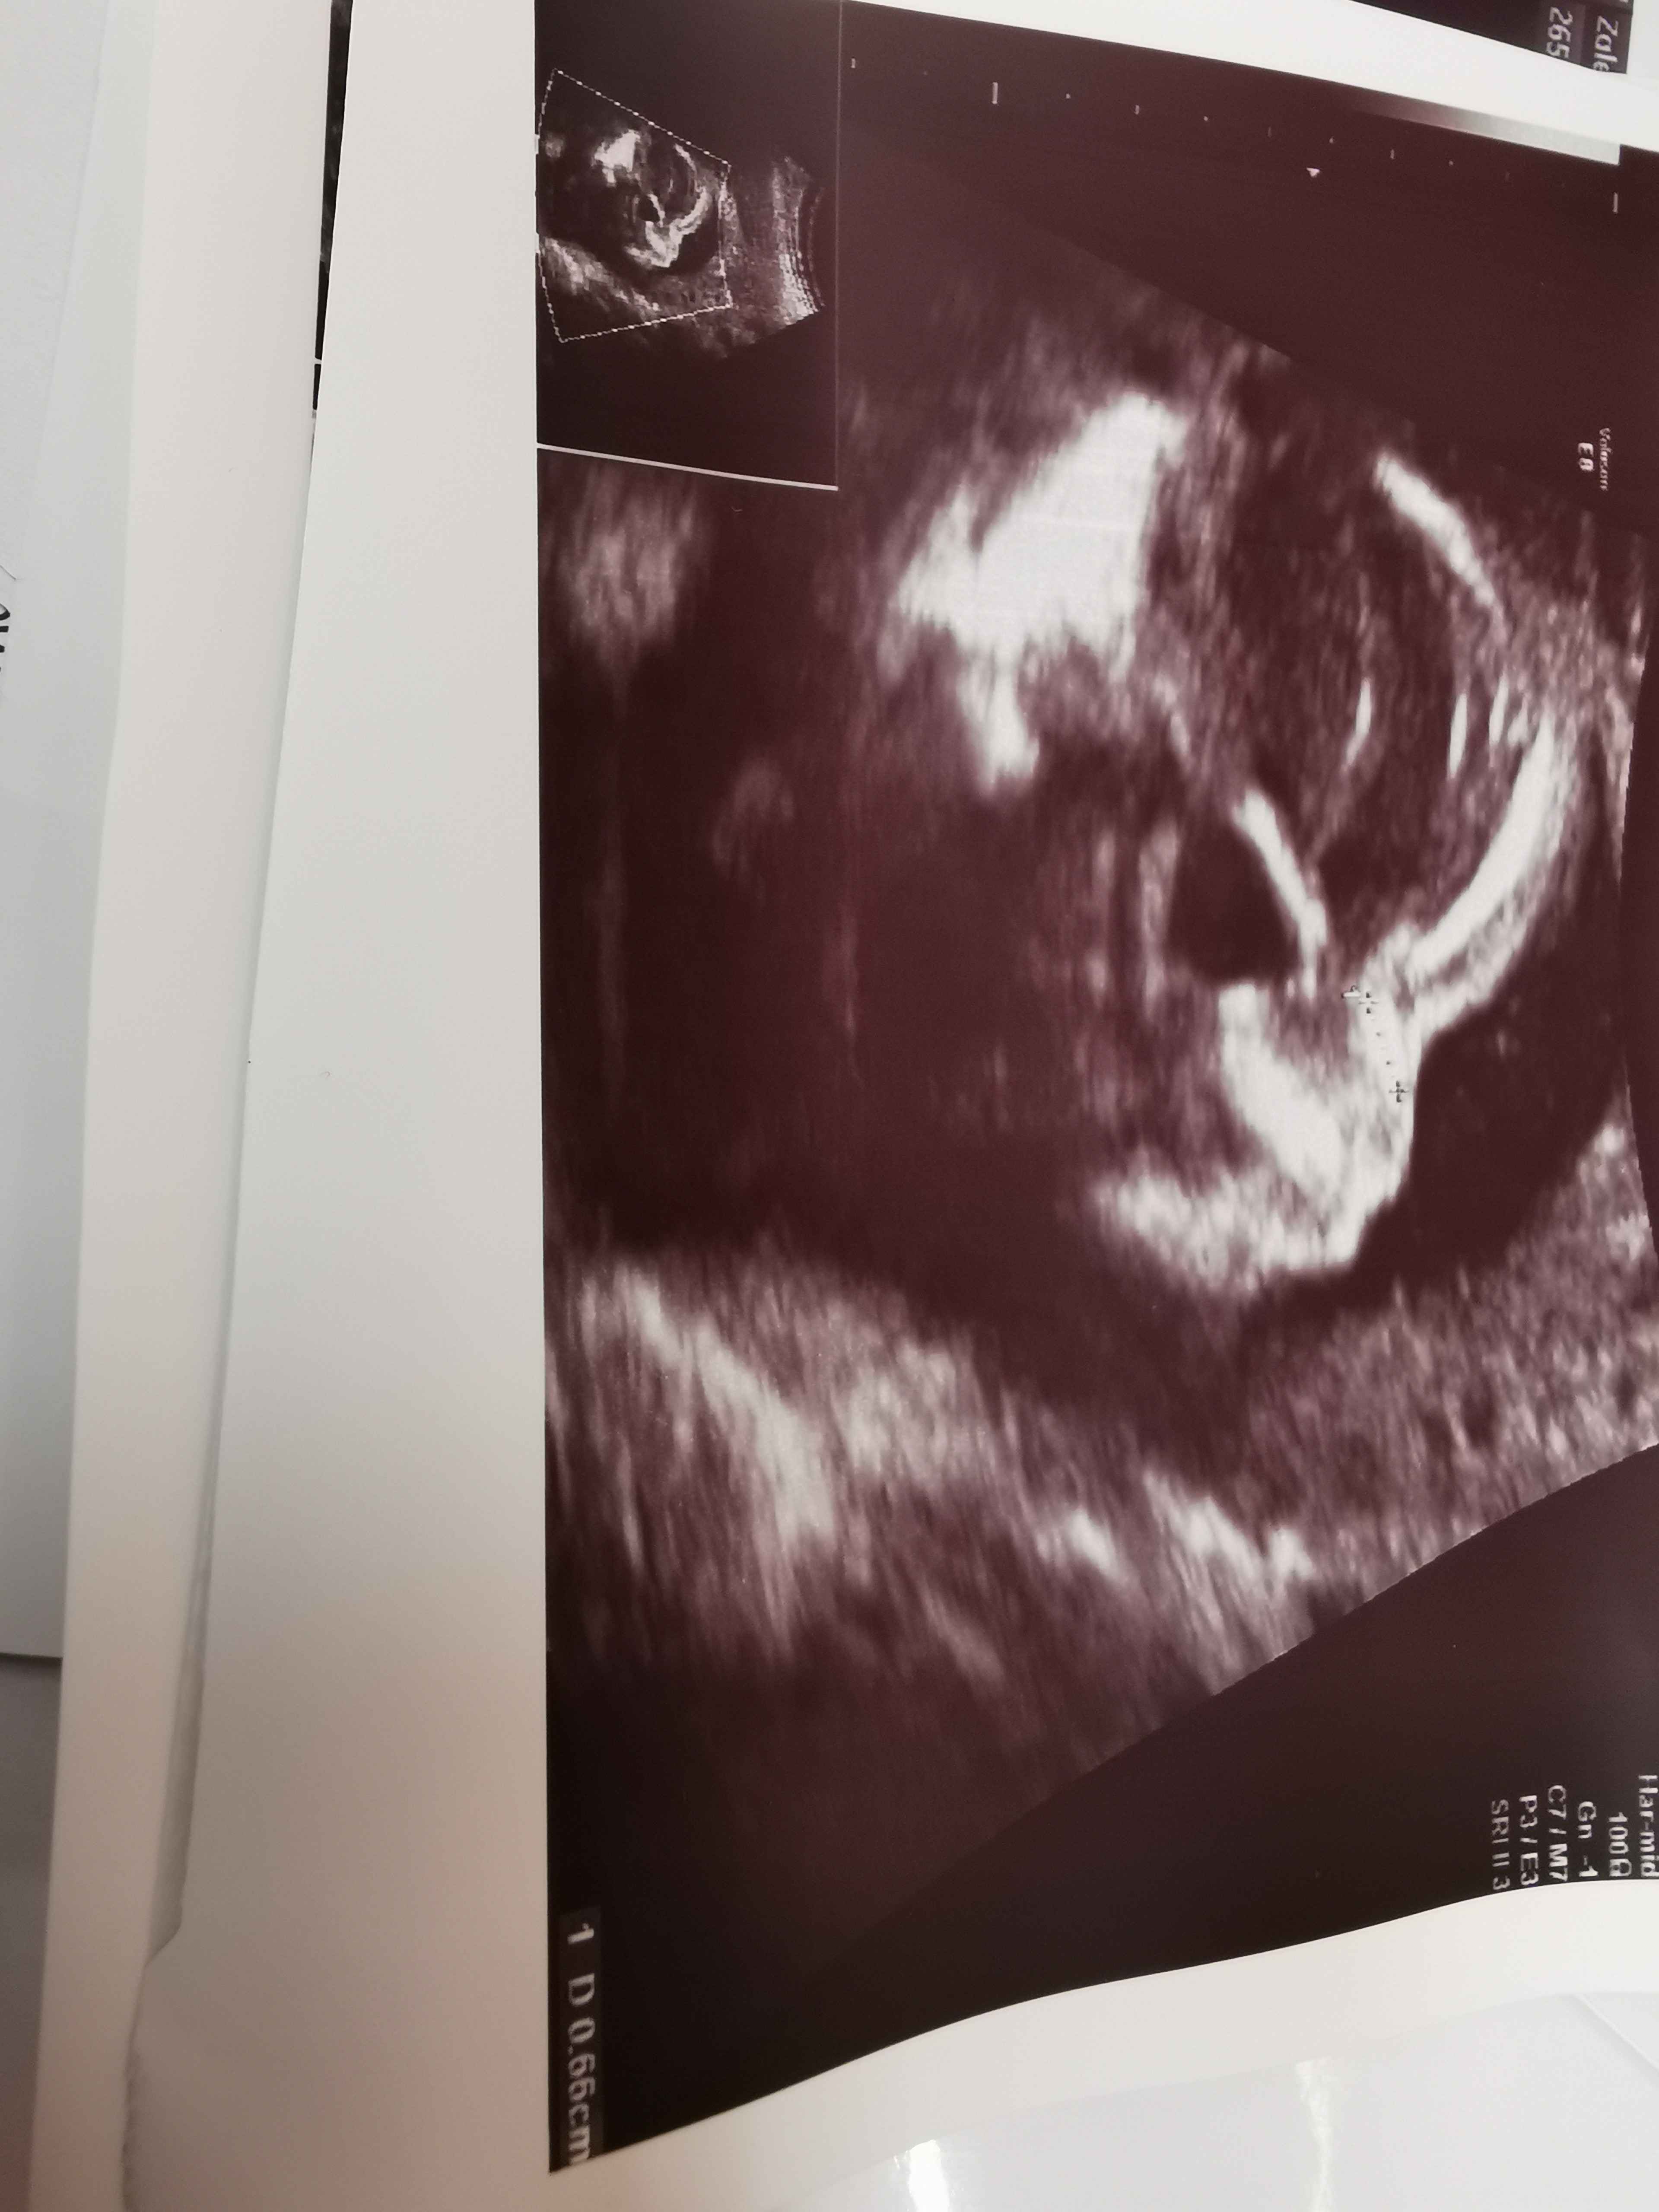

Wszystko dobrze❤️😊Dziecię ma wszystko prawidłowo, nie ma się podobno do czego doczepić 😊Uff!!! Rosnie szybciej niż wskazywal by wiek, bo większość parametrów ma tak, jakby miał skończony 21 tc, a jest o tydzień wcześniej 😊Waży 410g, szok!!! 😊ale współpracować nie chciał 😉Lekarz beznadziejny, o wszystko musialam sama pytać, bo sam z siebie nie mówił nic...

• IMG_20200616_094356_1.jpg

IMG_20200616_094356_1.jpg

2,1 MB · Wyświetleń: 88